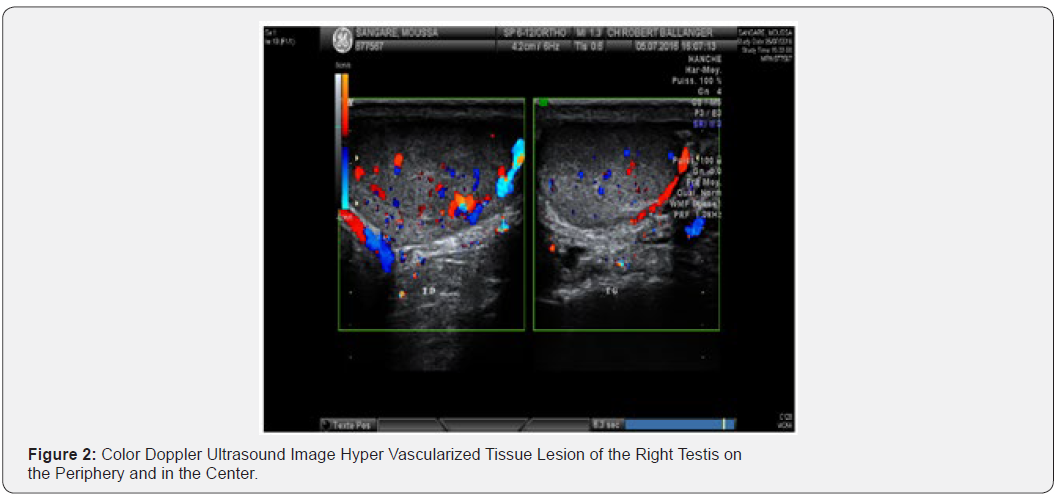

We report the case of a 37-year-old patient, who was admitted to our structure for treatment of right testicular pain that has been evolving for 4 months. The patient’s history mainly included sickle cell disease. Clinical examination revealed a left testicle of normal consistency, a straight testis increased in volume without palpable nodules but of much firmer consistency than on the left. The scrotal ultrasound revealed this right intra-testicular tissue lesion, of regular contours, occupying almost the whole of the testicular parenchyma, measuring in its large dimensions 33.4 X 17 mm (Figure 1), This nodule is vascularized on the periphery and in the center (Figure 2). Left testicle and epididymis of strictly normal ultrasound appearance. Tumor biomarkers (αFP, βHCG, and LDH) were normal. We decided to do a thoraco abdominal CT that does not find metastasis at a distance, and two sperm samples for selfpreservation at the CECOS level. Faced with these elements a right inguinal orchidectomy after clamping first cord was performed. The postoperative course was simple.